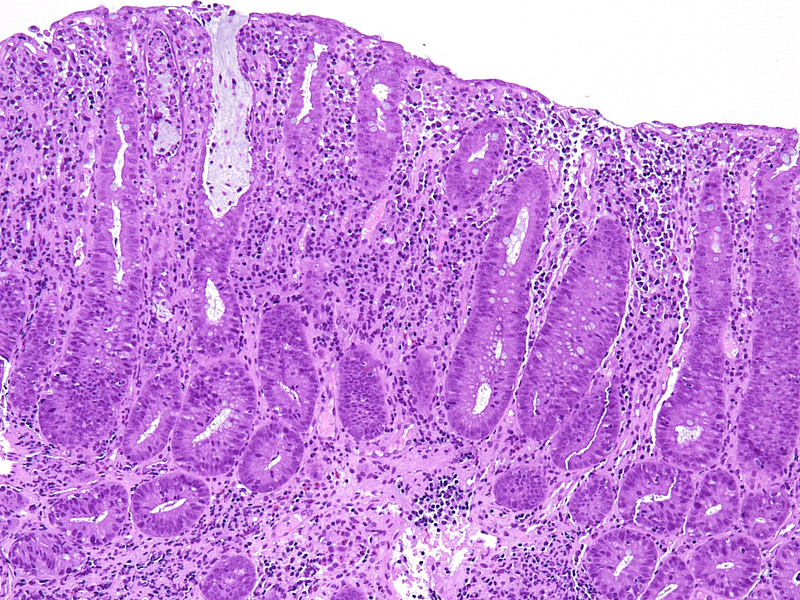

Histology showed mild crypt architecture distortion, increased lamina propria cellularity with mixed inflammatory cell infiltration containing plasma cells, lymphocytes, neutrophils, and scattered eosinophils. Mild basal plasmacytosis was present. The superficial epithelium was flattened and focally eroded (Panels A-B). Crypts showed a prominent loss of goblet cells, with reduced secretion from the remaining ones. Neutrophilic cryptitis with the presence of apoptotic bodies in the epithelial lining was observed. Some crypts were attenuated, lined by flattened epithelium, and contained apoptotic debris and neutrophils. Scattered withering crypts were found (Panels C-D).

These morphological findings of chronic active colitis with increased crypt epithelial apoptosis are suggestive of drug-induced colonic mucosa injury. Considering the patient’s known drug history of Pembrolizumab, Ipilimumab, and Nivolumab treatment, the diagnosis of immune checkpoint-inhibitor (ICI) therapy-associated colitis was made.